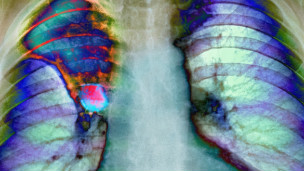

یوه څېړنه ښيي، چې په هرو درېیو کسانو کې یو کس په یوه ډول نه یو ډول پخپل ژوند کې د سرطان ناروغۍ نښې نښانې لري.

د سرطان ناروغۍ ته په کتلو سره، دغه ناروغي په بې وزلو او شتمنو دواړو هېوادونو کې ډېره شوې ده، چې په دغې ناروغۍ اخته کسانو لکه د اعدامېدونکو کسانو په سترګه کتل کېږي.

د یوګندا دغه روغتیايي مرکز ته د ناروغو مراجعینو شمېر په کمېدا دی، دغه مرکز هر کال نژدې ۲۲ زره مریضان تداوي کوي، چې ۲۰ زره یې د خطرناکو ناروغیو له کبله مري.